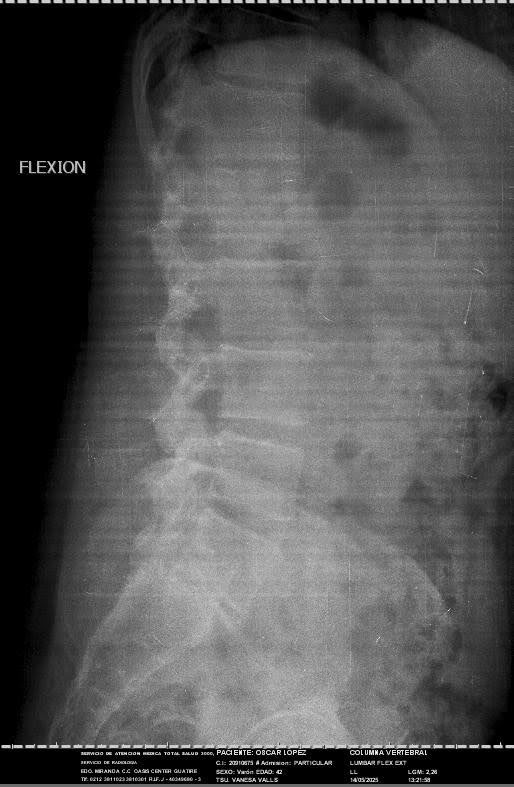

Hello, my name is Oscar. I am 43 years old. I am an orchestral trumpet player, for more than 15 years I was part of the Simon Bolivar Symphony Orchestra, representing Venezuela in thousands of concerts around the world. Today I need your help, due to the economic situation my country is going through, I cannot afford the materials for the arthrodesis I need for my spine surgery. I have been diagnosed with a lumbar disc herniation at the L4-L5 level, accompanied by grade I spondylolisthesis at the L5-S1 level. This has caused severe compression of the lumbar nerve roots, causing constant pain, loss of mobility, and paresthesia. My condition has been evaluated by the medical team, who has indicated the need for imminent spinal surgery.

• L4-L5 discectomy

• Decompressive laminectomy

• Placement of instrumentation (screws, rods, a cross connector, and a specialized cage)